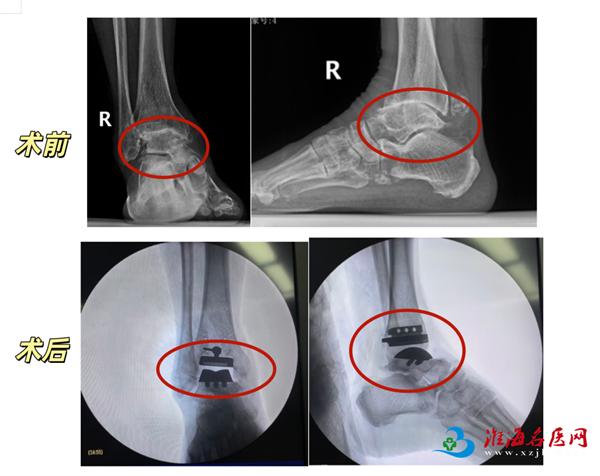

团队融入精准微创理念,在术前利用三维CT影像数据进行个体化设计,并借助3D打印技术制作了手术导板,以实现假体的精准安放。术中,医生在有效清除病变组织的同时,尽可能保护了关节周围重要的韧带和软组织,为术后关节的稳定性与功能恢复打下了基础。得益于精准的术前规划和微创的手术操作,患者术后得以在专业指导下早期开始康复锻炼,缩短了恢复周期。

术后3—4周,两位患者踝关节疼痛已显著减轻,可正常活动。

王爱国介绍,全踝关节置换术是治疗终末期踝关节疾病的重要手段之一。其核心是通过人工假体重建一个无痛、稳定且具有活动功能的踝关节。

简单来说,全踝关节置换术就是通过手术将受损的踝关节软骨和部分骨组织替换为人工假体,模拟正常踝关节的结构和功能,从而彻底解除疼痛、矫正畸形、恢复关节活动度的一种微创手术。